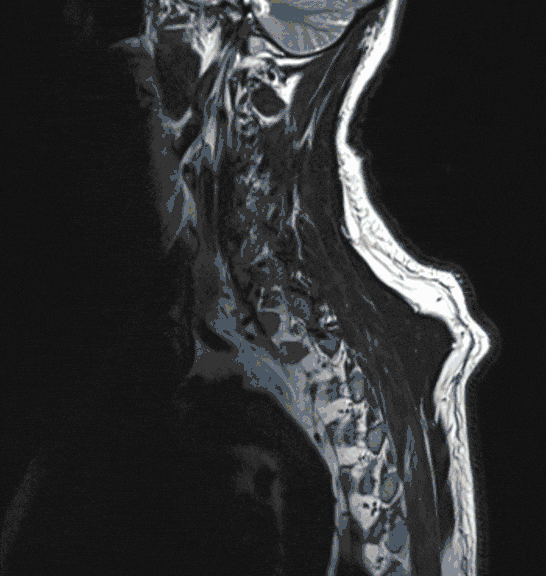

Meningeome sind nicht seltene Tumore, die das Rückenmark von außen bedrohen. Aufgrund ihres meist langsamen Wachstums können sie zu einer erheblichen Größe heranwachsen und dadurch die Funktion des Rückenmarks bedrohen. Sie werden deshalb meist spät erkannt, häufig erst nach Auftreten von starken Schmerzen oder Gangstörungen.